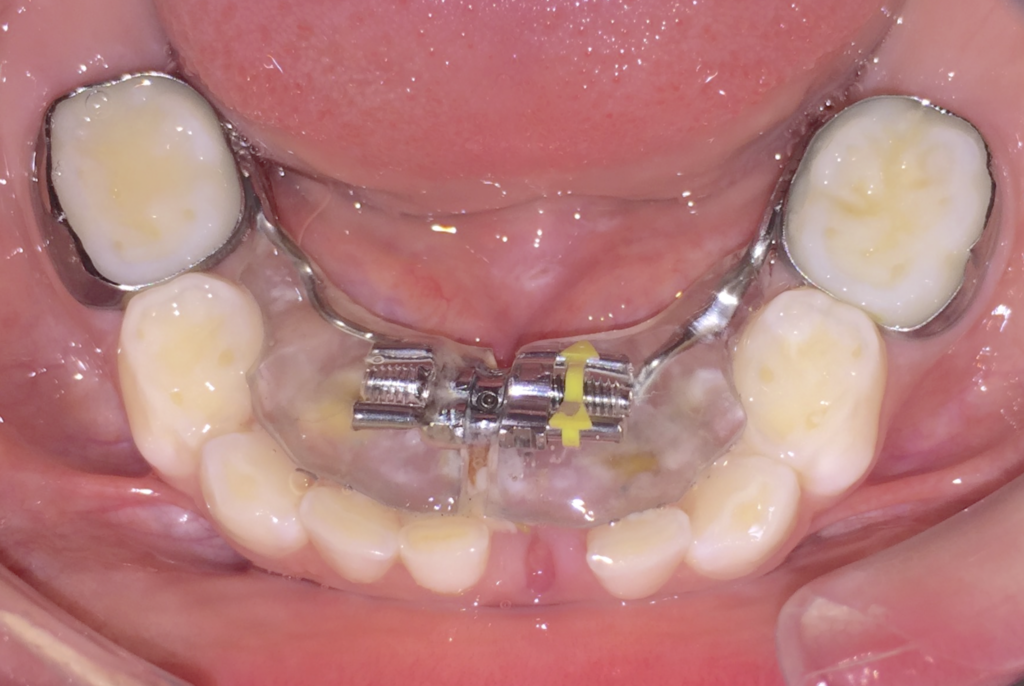

9. Microcargol afluixat, amb moviment o inflamació

En els tractaments amb aparells amb suport ossi, els cargols poden perdre força degut a restes de menjar que provoquen inflamació.

Si es dóna el cas, realitzeu els passos següents:

1. Contacteu amb la clínica Boca a Boca i agafeu hora amb la Dra. Villa. Els cargols són un tema quirúrgic i la Dra. Cubells no us pot ajudar en aquest sentit.

2. Higiene molt exhaustiva de la zona, especialment amb el fil dental i/o els raspallets interdentals. (Podeu mullar el fil o el raspallet amb clorhexidina).* Instruccions d’higiene

3. Apliqueu Gel de clorhexidina la llaga, després de cada raspallat i a demanda entre raspallats si cal.* (Producte complementari a les instruccions d’higiene; ells sols NO solucionaran la inflamació).

Microcargol anclat

Microcargol afluixat